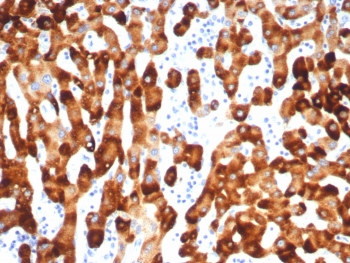

IHC staining of FFPE human HBV-infected liver with HBsAg antibody (clone HBsAG/7666R). HIER: boil tissue sections in pH 9 10mM Tris with 1mM EDTA for 20 min and allow to cool before testing.

Applications Immunohistochemistry (FFPE) : 1-2ug/ml for 30 min at RT